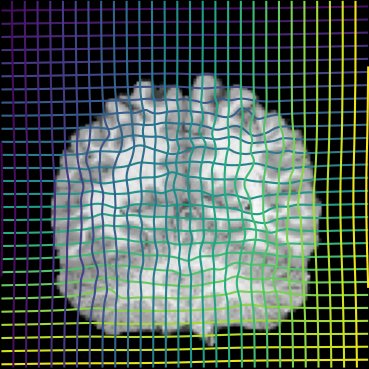

Inverse consistent rigid, affine, nonparametric, and MLP registration. We train networks on MNIST 5s using the methods in Secs. 3 and 4, demonstrating that the resulting networks are inverse-consistent. Our TwoStepConsistent (TSC) operator can be used on any combination of the networks defined in Sec. 3. For demonstrations, we join an MLP registration network to a vector field registration network, and join two affine networks to two vector field networks. Fig. 2 shows successful inverse-consistent sample registrations.

Affine registration convergence. In addition to being inverse consistent, our method accelerates convergence and stability of affine registration, compared to directly predicting the matrix of an affine transform. Here, we disentangle whether this happens for any approach that parameterizes an affine transform by taking the exponent of a matrix, or whether this acceleration is unique to our inverse consistent method. We also claim that multi-step registration is important for registration accuracy and convergence time and that an inverse consistent multi-step operator, TwoStepConsistent, is thus beneficial.

To justify these claims, we investigate training for affine registration on the synthetic Hollow Triangles and Circles dataset from [23] while varying the method used to obtain a matrix from the registration network and the type of multi-step registration used. To obtain an affine matrix, we either directly use the neural network output , use , or, as suggested in Sec. 3, use . We either register in one step, use the TwoStep operator from [7, 23], or use our new TwoStepConsistent operator. This results in 9 training configurations, which we run 65 times each.

We observe that parameterizing an affine registration using the construction speeds up the first few epochs of training and gets even faster when combined with any multi-step method. In Fig. 3, note that in the top-left corner of the first plot, the green loss curves (corresponding to models using ) are roughly vertical, while the other loss curves are roughly horizontal, eventually bending down. After this initial lead, these green curves also converges to a better final loss. Further, all methods that use the construction train reliably, while other methods sometimes fail to converge (Fig. 3, right plot). This has a dramatic effect on the practicality of a method since training on 3-D data can take multiple days on expensive hardware.

Finally, as expected, the only two approaches that are inverse consistent are the single-step inverse consistent by construction network, and the network using two inverse-consistent by construction subnetworks, joined by the TwoStepConsistent operator. (Fig. 3, middle, dotted and solid green).